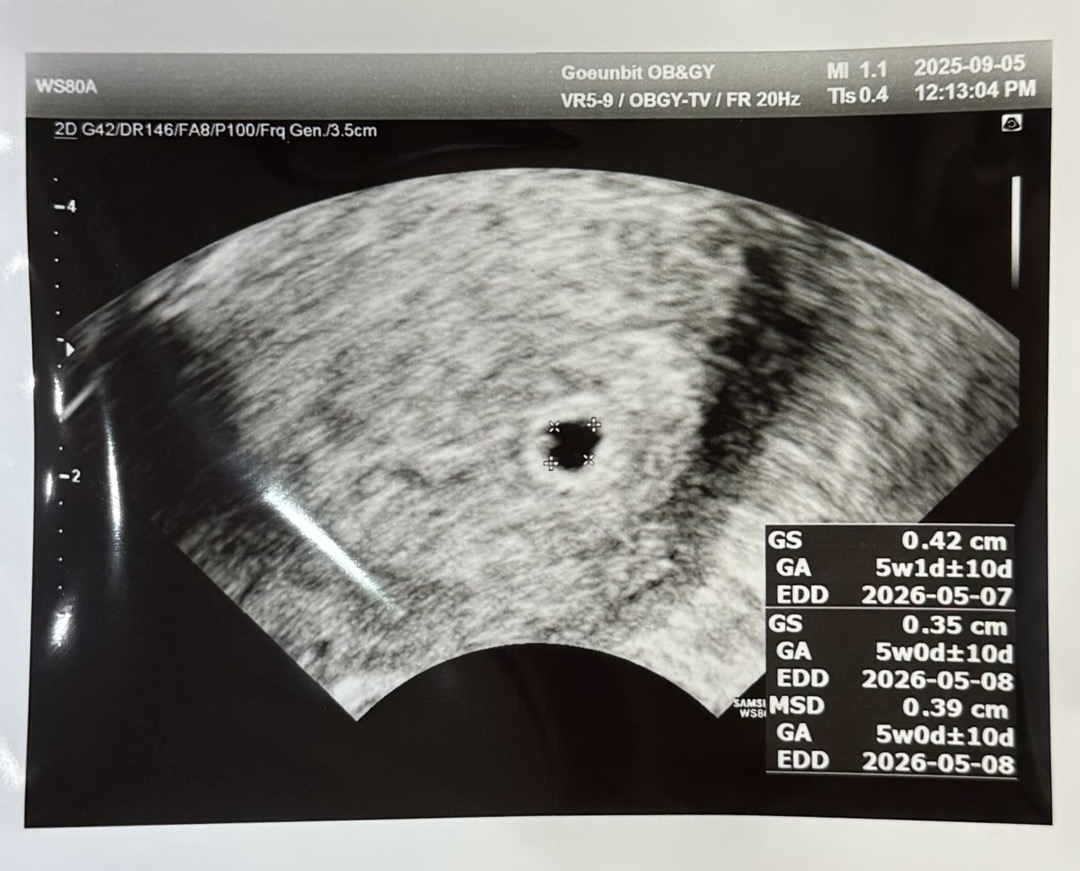

오늘 5주0일차 아기집 확인하고 왔어요~~!